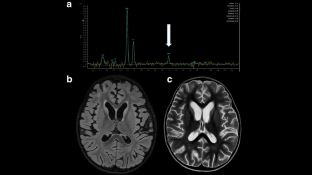

Acute Encephalopathy with Biphasic Seizures and Late Reduced Diffusion (AESD) is a rare neurological disorder associated with infection, primarily diagnosed in Japanese children, characterized by biphasic seizures, restricted diffusion on magnetic resonance imaging (MRI), and neurological decline. We report an Italian case and provide a scoping review of cases published outside Japan in comparison with Japanese literature, using distinct sets of inclusion criteria as the reported incidence and quality of studies are different. Clinical and epidemiological characteristics are analyzed. Potential factors contributing to this unusual epidemiology are investigated. Our case (3-year-old girl) conforms to typical AESD features. AESD is very rarely reported outside Japan, where only 29 cases have been published (17 female, 2.6 ± 2.7 years). Their features closely resemble the Japanese patients. The only relevant difference is the infectious trigger distribution, with Human herpesvirus-6 (HHV6) predominantly reported in Japan (38.2%), but not in other areas. The morbidity of AESD extends beyond Japan, but it is probably underestimated with rare cases reported globally. Multicenter international studies are needed to clarify the AESD incidence around the world and their related genetic and environmental factors and to promote internationally shared diagnostic criteria and guidelines for acute encephalopathies including AESD.

AESD features are biphasic seizures, MRI restricted diffusion, and neuroregression.